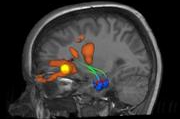

INSTITUTE OF COGNITIVE NEUROLOGY AND DEMENTIA RESEARCH